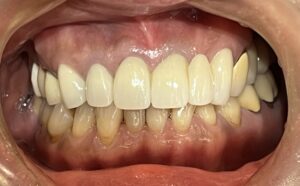

本日は、ジルコニアセラミック(歯科用人工ダイヤモンド)を使用した

メタルフリー治療の症例をご紹介いたします。

治療前は、メタルの詰め物が多数入っておりましたが、

患者様より詰め物を白くキレイにしたいとのことで治療を行いました。

Before After

メタルフリーになり、お口の印象がとても明るくなりました!

メタルフリー治療を行うと、審美的な改善が大きいですが

それだけではありません!

詰め物、被せ物にジルコニアセラミックを使用することで

経年的な摩耗や変色を最小限に抑える、

金属アレルギーのリスクがない、

歯質との適合性が高く、むし歯の再発リスクが低いなど、様々なメリットがあります。

前歯のレイヤリングジルコニアは特に色味や形態をぴったり合わせるため、

セラミストが写真撮影、デジタルトライインを行って作成します。

笑顔がさらに素敵になりましたね✨

患者様にも、とても喜んでいただけました😊